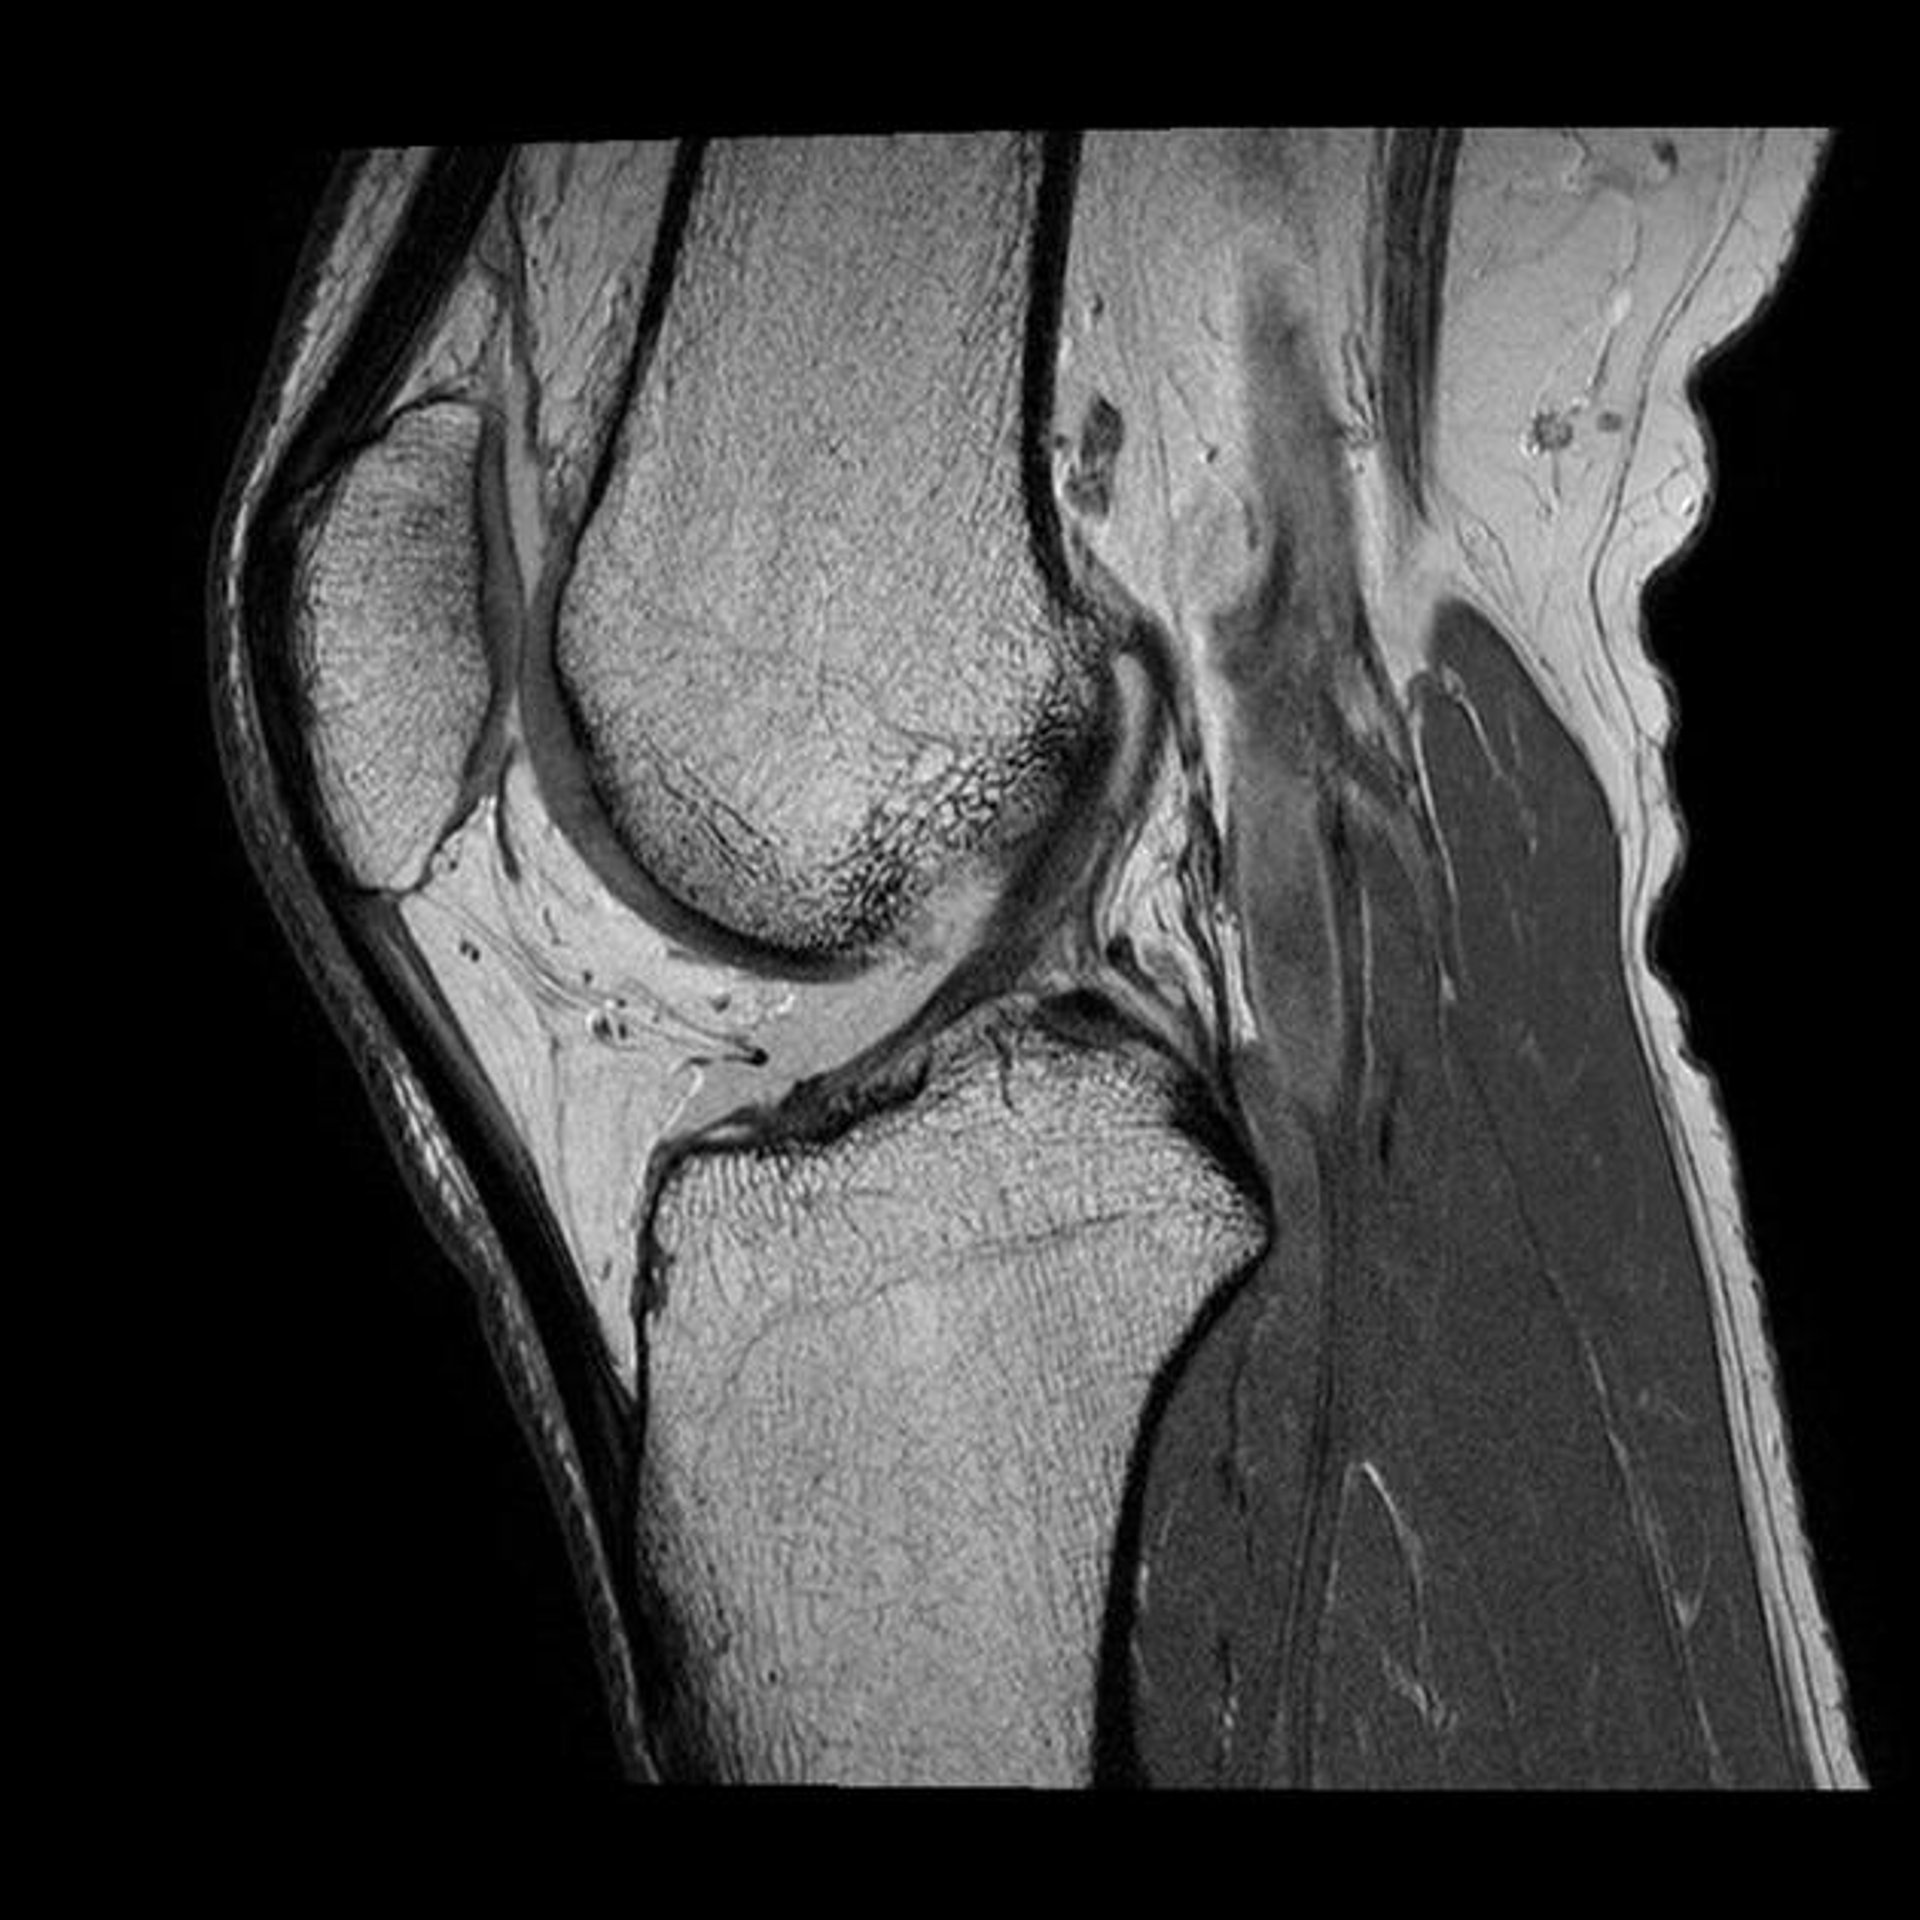

ACL Detection

Detect ruptured ACLs with precision and accuracy.

Osteoarthritis Insights

Analyze knee osteoarthritis for better treatment decisions.